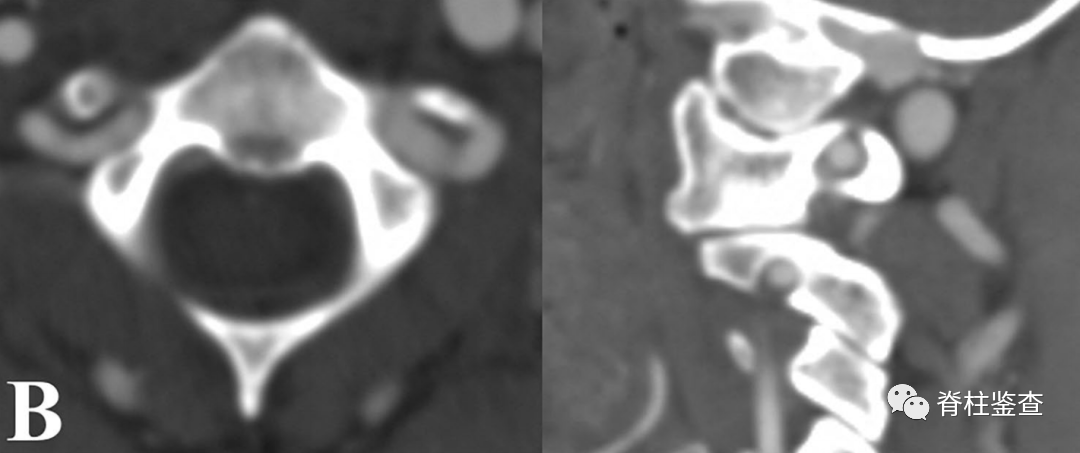

B:椎弓根狭窄,椎动脉高跨右侧椎弓根螺钉置入风险高

B:椎弓根狭窄,右侧椎动脉高跨